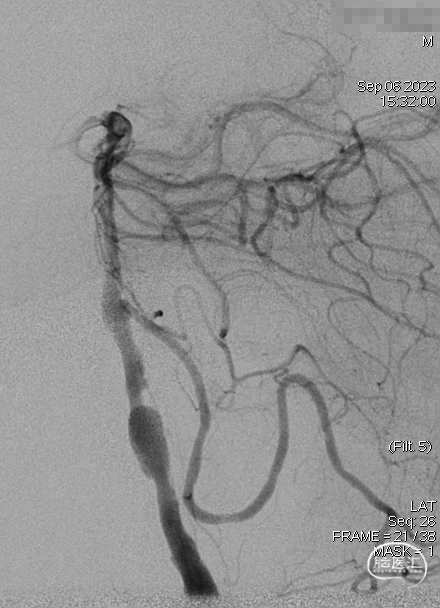

DSA示双侧椎动脉V4段狭窄,右侧为著且合并梭形动脉瘤。

术前DSA。